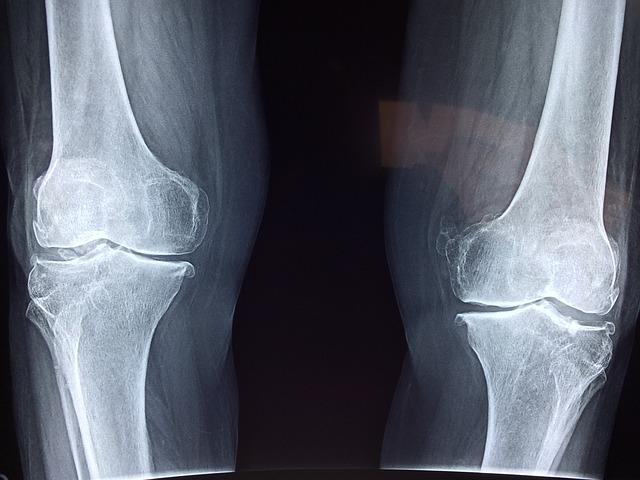

The anterior cruciate ligament (ACL) is a crucial component of knee stability in soccer players. Without a healthy ACL, players may struggle with balance, agility, and overall performance on the field.

In soccer, the ACL plays a significant role in preventing the knee from twisting or hyperextending during quick movements, such as cutting, pivoting, and sprinting. A strong ACL not only helps athletes perform at their best but also reduces the risk of serious knee injuries, such as ACL tears.

When it comes to knee stability, the anterior cruciate ligament (ACL) plays a crucial role in keeping the knee joint in place. The ACL is one of the major ligaments in the knee, providing stability and support during activities that involve twisting, turning, and jumping. Without a properly functioning ACL, the knee joint can become unstable and prone to injury.